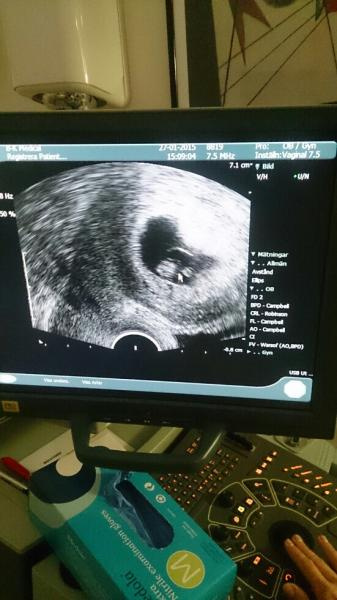

Det var allt en liten krabat där inne med ett tickande hjärta. Nu får vi hoppas att detta går vägen denna gången. Blev tillbaka flyttad en dag bf 10/9

Ja känns härligt o få de bekräftat att allt ser bra ut, är i v7+4 idag:)

Läste att hjärtat börjar ticka i vecka 6.. Så häftigt när man tänker på det tycker jag!

Att allt utvecklas så tidigt när plutten bara är någon millimeter stor <3